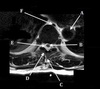

10

Q

What is letter A?

A

11

What is letter B?

12

What is letter C?

13

What is letter D?

14

What is letter E?

15

What is letter F?

16

What is letter G?

17

What is letter H?

18

What is letter J?